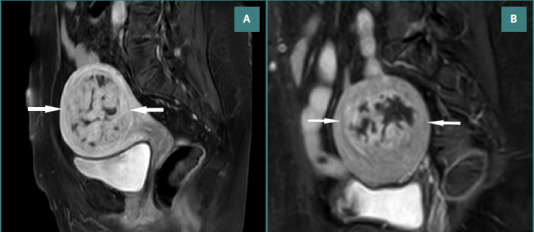

本研究的目的是比较使用非球形聚乙烯醇颗粒(nsPVA)或三丙烯-明胶微球(TAGM)子宫动脉栓塞(UAE)后盆腔MRI的平滑肌瘤梗死率和栓塞成功率。回顾性分析141例(平均年龄38岁)接受标准双侧UAE合并nsPVA (n = 80)或TAGM (n = 61)的患者。栓塞成功的定义是所有可识别的肌瘤完全梗死。采用Mann-Whitney U检验和独立样本t检验比较数据类型。进行二元逻辑回归。556个肌瘤被评估,子宫中位体积为435 cm3,优势肌瘤中位体积为110 cm3。两组患者的基线特征包括年龄(P = 0.446)、子宫体积(P = 0.148)、显性肌瘤体积(P = 0.124)和非梗死性肌瘤数量(P = 0.092),差异无统计学意义。nsPVA组和TAGM组的肿瘤梗死率分别为74%(251/337)和79%(174/219),两者基本相似(P = 0.191)。同样,两组的栓塞成功率相似(nsPVA和TAGM分别为67.5%和72.1%,P = 0.589)。初步非梗死肌瘤数量与栓塞成功率呈负相关(P = 0.035)。本研究评估了这两种物质的可用性和副作用,并对患者进行了6个月的MRI随访,以评估可能的后果。根据栓塞后的MRI, nsPVA和TAGM的平滑肌瘤梗死和栓塞成功率相似。子宫和肌瘤体积的减少与两种药物相似。

The aim of this study was to compare leiomyoma infarction rates and embolization success using pelvic MRI following uterine artery embolization (UAE) using non-spherical polyvinyl-alcohol particles (nsPVA) or tris-acryl-gelatin microspheres (TAGM). A retrospective analysis was performed in 141 patients (mean age, 38 years) who underwent standard bilateral UAE with either nsPVA (n = 80) or TAGM (n = 61). Embolization success was defined as complete infarction of all discernible fibroids. Mann-Whitney U and independent-sample t-test were used to compare data types. A binary logistic regression was performed. 556 fibroids were evaluated, with a median uterine volume of 435 cm3 and a median dominant fibroid volume of 110 cm3. There were no significant differences between the two groups regarding baseline characteristics, including age (P = 0.446), uterine volume (P = 0.148), dominant myoma volume (P = 0.124), and non-infarcted myoma number (P = 0.092). The tumor infarction rate in the nsPVA and TAGM groups was 74% (251/337) and 79% (174/219), respectively, which was approximately similar (P = 0.191). Likewise, embolization success was similar among both groups (67.5% vs. 72.1% for nsPVA and TAGM, respectively, P = 0.589). There was an inverse relationship between the number of preliminary non-infarcted myomas and embolization success rate (P = 0.035). This study assessed the availability and side effects of these two substances, and patients underwent a 6-month follow-up MRI to evaluate possible consequences. According to post-embolization MRI, the leiomyoma infarction and embolization success rates for nsPVA and TAGM were similar. The decrease in uterine and myoma volumes was analogous to both drugs.